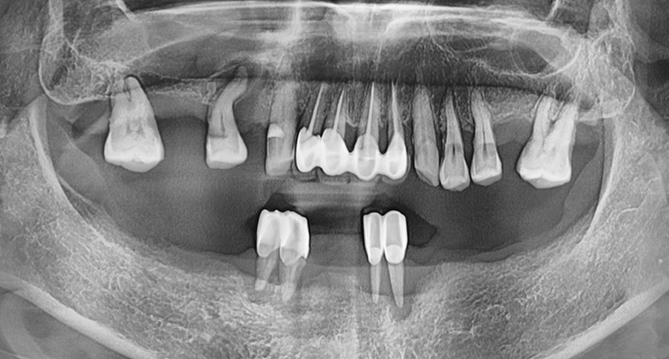

연세새빛치과 전체치아교정[클리피씨] 교정 전

연세새빛치과 전체치아교정[클리피씨] 교정 후